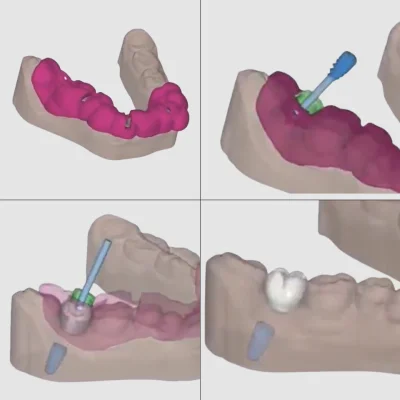

- โปรแกรมจะสร้าง Surgical Guide (ไกด์นำร่องการผ่าตัด) ซึ่งเป็นอุปกรณ์เฉพาะบุคคลที่ใช้เป็นแม่พิมพ์ในการนำทางหัวกรอระหว่างการผ่าตัด เพื่อให้การฝังรากเทียมเป็นไปตามแผนที่วางไว้

2. ผ่าตัดฝังรากฟันเทียมแบบ Digital Guided Surgery

- ทันตแพทย์จะให้ยาชาเฉพาะที่ และวาง Surgical Guide ที่ออกแบบมาโดยเฉพาะลงบนเหงือกของคนไข้

- ทำการเจาะรูในกระดูกตามตำแหน่งและองศาที่แม่นยำตามไกด์นำร่อง

- ขั้นตอนนี้ใช้เวลาสั้นกว่าและมีความแม่นยำสูง ทำให้เจ็บน้อย และลดอาการบวมช้ำหลังการผ่าตัดได้ดี